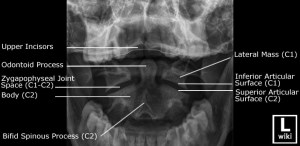

Anatomy of x ray chest